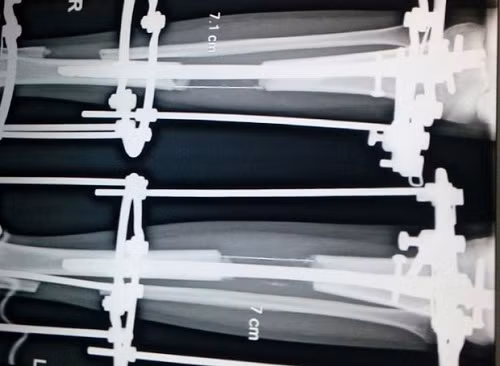

![]() |

| Phim chụp X-quang một đoạn xương chân đang được kéo dài ở Ấn Độ. Ảnh: Bác sĩ Sarin |

Ngày nay, kỹ thuật của Ilizarov được các bác sĩ phẫu thuật khắp Ấn Độ sử dụng, mặc dù có nhiều cải tiến làm cho nó nhanh hơn và ít đau đớn hơn. Bác sĩ Sarin từng giành giải thưởng quốc tế danh giá, cho biết ông đã phải trăn trở suy nghĩ đến giá trị đạo đức khi thực hiện ca phẫu thuật đầu tiên.